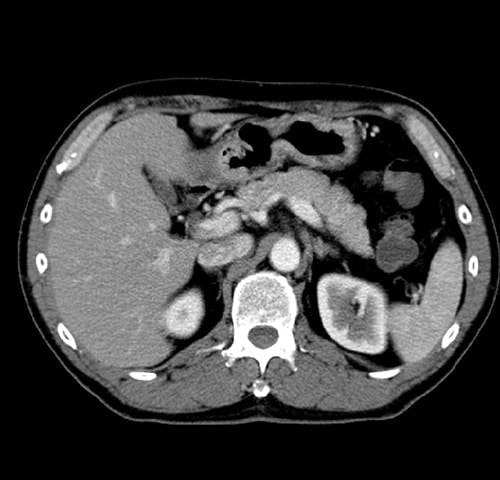

X線を周囲よりらせん状に照て、全身の断層写真(輪切りの写真)を数秒で撮り各臓器を詳細に検査します

X線を周囲よりらせん状に照て、全身の断層写真(輪切りの写真)を

数秒で撮り各臓器を詳細に検査します。

・ 腹部(肝臓・胆のう・ 膵臓・腎臓)病変

腹部